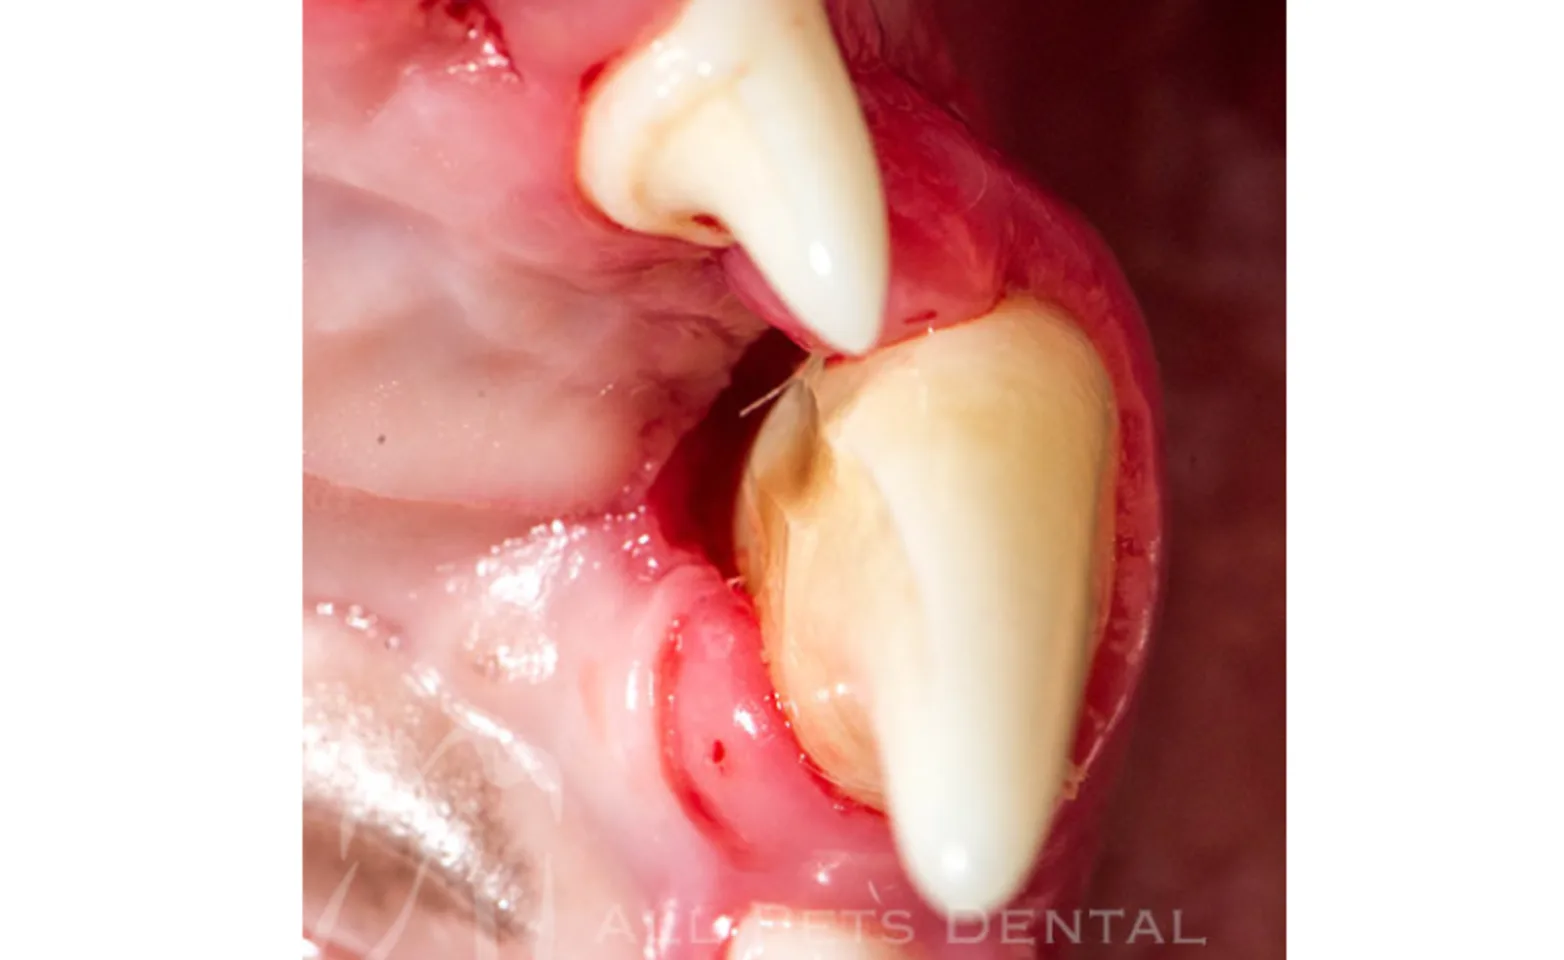

Gingival Recession

Gingival recession occurs secondary to periodontal disease exposing the tooth root(s). If the tooth is also mobile, extraction is the treatment of choice.